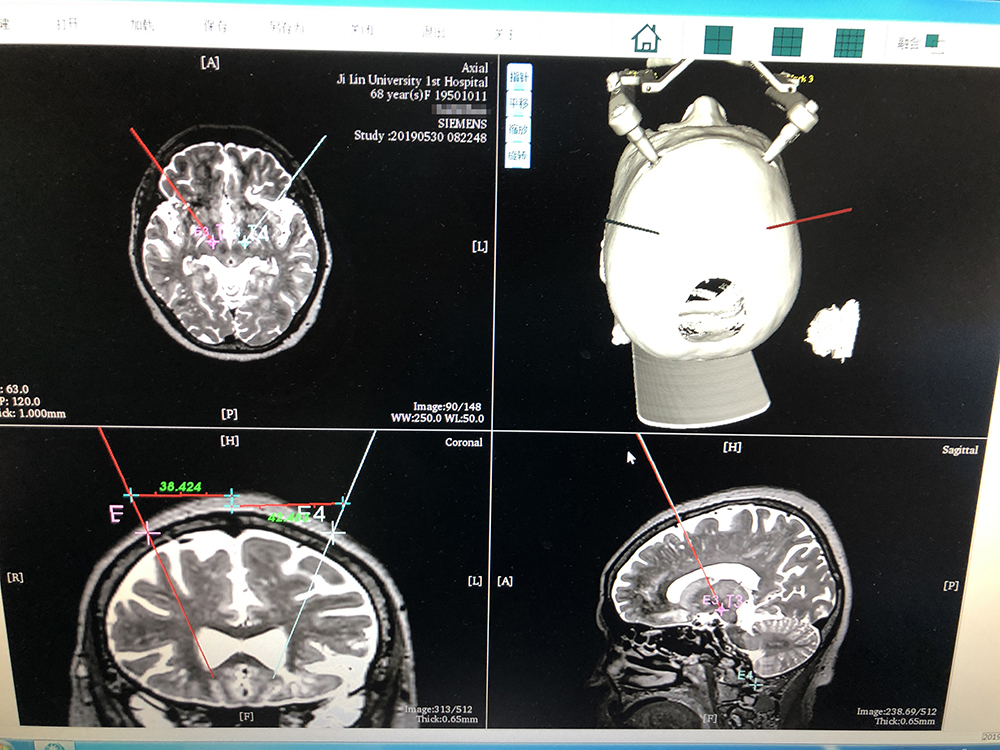

術(shù)前,邱吉慶教授借助“睿米”神經(jīng)外科手術(shù)機器人配套軟件,為患者制定雙側(cè) STN 核團植入電極的手術(shù)路徑規(guī)劃。

借助“睿米”軟件制定手術(shù)規(guī)劃

手術(shù)規(guī)劃完成后,分別完成機械臂注冊和患者注冊,系統(tǒng)顯示注冊精度分別達到0.07和0.16,符合 DBS 手術(shù)臨床的高精度要求。為進一步確認,利用隨機驗證點進行精度驗證,確認誤差在1mm以內(nèi)。